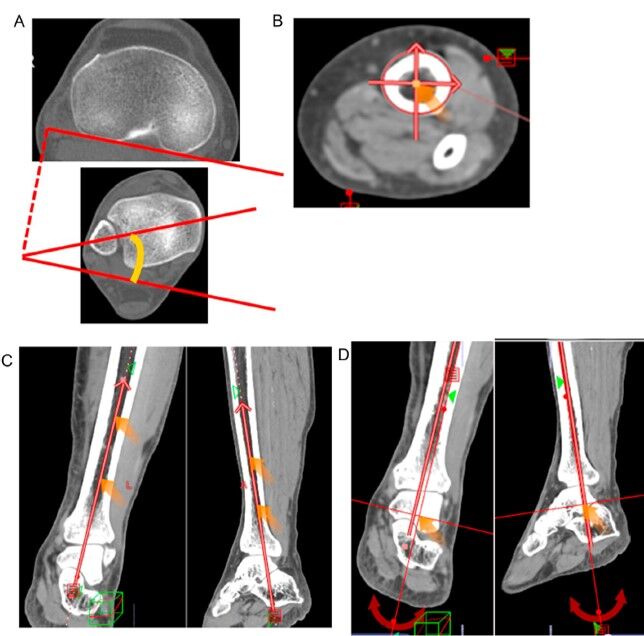

内容は高度内反変形膝に対するDouble level osteotomyの術後の回旋変化についてのCTによる解析です。

CTで大腿骨と脛骨それぞれの回旋を測定しました。

大腿骨は約2度の変化があり、脛骨は変化がほとんどないという結果でした。